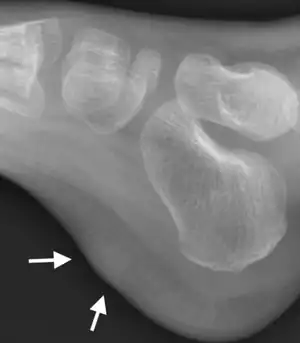

| Myositis ossificans and fibro-osseous pseudotumour of digits | ![]() | |